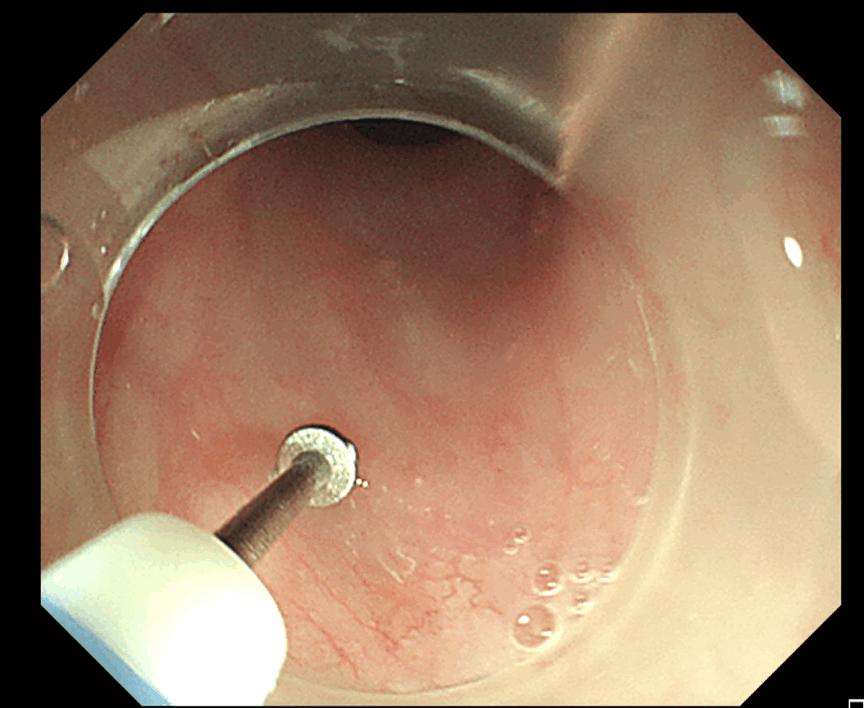

内镜经黏膜下隧道肿瘤切除术(submucosaltunnel endoscopic resection, STER)是治疗消化道固有肌层肿瘤的一种高难度内镜微创治疗技术。通俗地讲

就是医生在消化道黏膜表面

切开一个入口

随后将内镜深入其中

在黏膜下层建立一个“隧道”通路

直达病灶

在仪器直视下将肿瘤切除

并将肿瘤从入口取出

最后

用钛夹将“隧道”开口闭合的手术过程

该手术与传统开胸手术相比,不仅能够避免切除食管,而且具有手术时间短、创伤小、痛苦小、费用低、恢复快的优点。8月12日下午,周平红教授来到吴淞医院,亲自主刀,带领内镜团队,在食管壁内打通了一条“隧道”,仅用时46分钟,就成功为孙先生摘除了肿瘤。